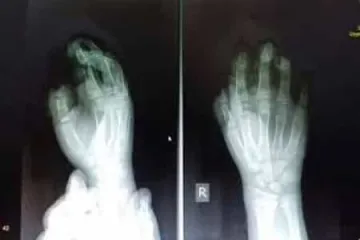

Պայթուցիկից տուժած երեխայի երկու մատը վերականգնվել է

Հրապատիճը պայթել է 9-ամյա աղջնակի ձեռքի մեջ եւ հարվածել դեմքին. երեխան հիվանդանոցում է